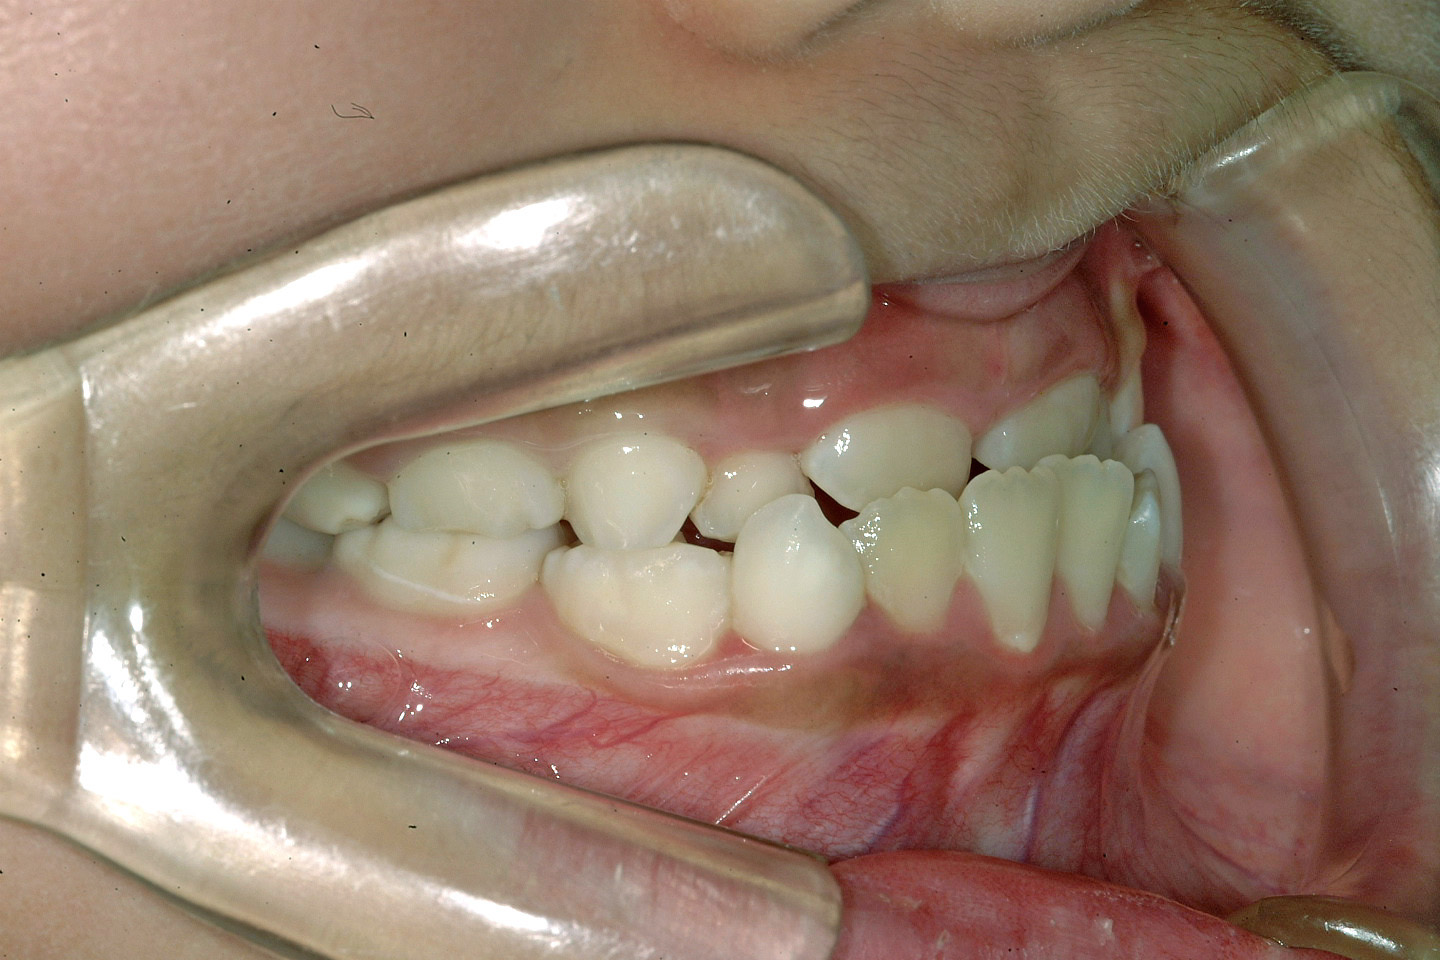

下顎前突(受け口)

叢生(乱ぐい歯)

受け口を主訴に来院された7歳の女子です。骨格性の反対咬合のため、早期の治療開始をおすすめいたしました。リンガルアーチとチンキャップの組み合わせで前歯部被蓋の改善を行いました。その後、経過観察を経てエッジワイズ装置(デーモンシステム)で後期治療を行っておりますが、非抜歯で、良好な結果を得ることができました。